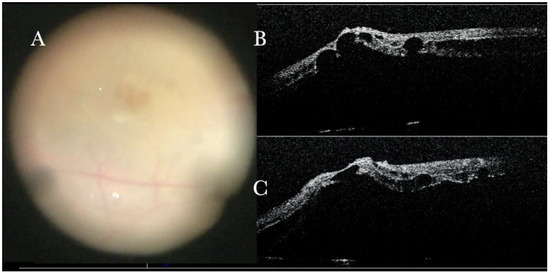

Figure 15.

Microscope view of the macular area in a case of retinal detachment associated with retinoschisis. This is the second operation for a relapse of retinal detachment. In the previous surgery, perfluorocarbon liquid (PFCL) was used. The surgeon was considering at this point whether point was (a) a cyst of a hole, (b) schisis or represented subretinal bands or PVR, or (c) indicated the presence of a subretinal PFCL bubble. It is very difficult to discriminate with the microscope view only.

i-OCT was helpful in discriminating retinal breaks (Figure 16), intraretinal cysts (Figure 16), and areas of schisis (Figure 17), and excluding subretinal PFCL in a relapsed RD secondary to retinoschisis that had previously undergone vitrectomy, PFCL, and silicone oil injection (Figure 18).

(A) Microscope view of point (a) of Figure 15. Microscope view of point (b) of Figure 15. (The green box indicates the field-of-view of the OCT scan, the green and blue lines within the green box show the vertical and horizontal scan planes). (B) The intraoperative optical coherence tomography (i-OCT) B horizontal (green) scan shows that, in the area of point (b), the suspect bands are areas of retinoschisis. (C) The i-OCT vertical scan shows that, in the area of point (b), the suspect bands are areas of retinoschisis.

Figure 18.

(A) Microscope view of point (c) of Figure 15. (The green box indicates the field-of-view of the OCT scan, the green and blue lines within the green box show the vertical and horizontal scan planes). (B) The intraoperative optical coherence tomography (i-OCT) horizontal (green arrow) scan shows that, in point (b), the suspect bubbles of perfluorocarbon liquid (PFCL) represent retinoschisis areas. (C) The i-OCT vertical scan shows that, in point (b), the suspect bubbles of PFCL represent areas of retinoschisis.